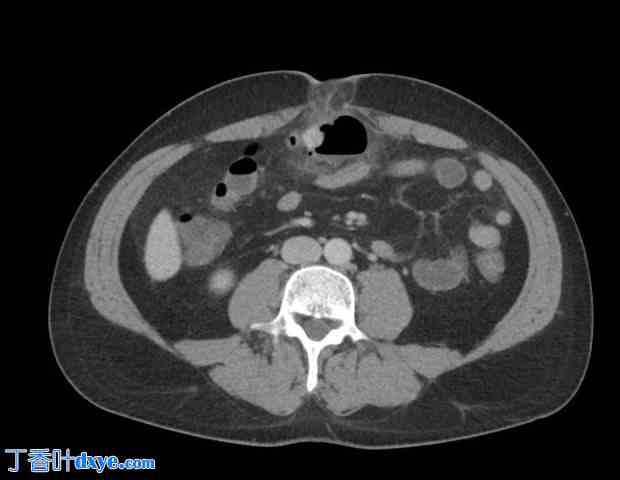

患者随后的诊断性检查显示白细胞增多(20 G/l)和C反应蛋白 (CRP) 升高(260 mg/l)。腹部超声检查显示脐疝嵌顿,但腹腔内无游离液体征象。为了进一步了解情况,对患者进行了腹部计算机断层扫描 (CT) 扫描(图 1、2)。放射科医生的检查结果如下:“脐疝嵌顿,主要表现为腹膜前盲肠极疝出,伴有缺血征象和个别小气体形成,但无法确定其所属的管腔。”

图 1. CT 扫描显示脐疝伴粪石和缺血征象。

轴向增强 CT 扫描显示脐疝,其中包含小肠袢和符合粪石(粪石)的圆形结构。周围脂肪条带提示炎症改变和缺血的早期征象。